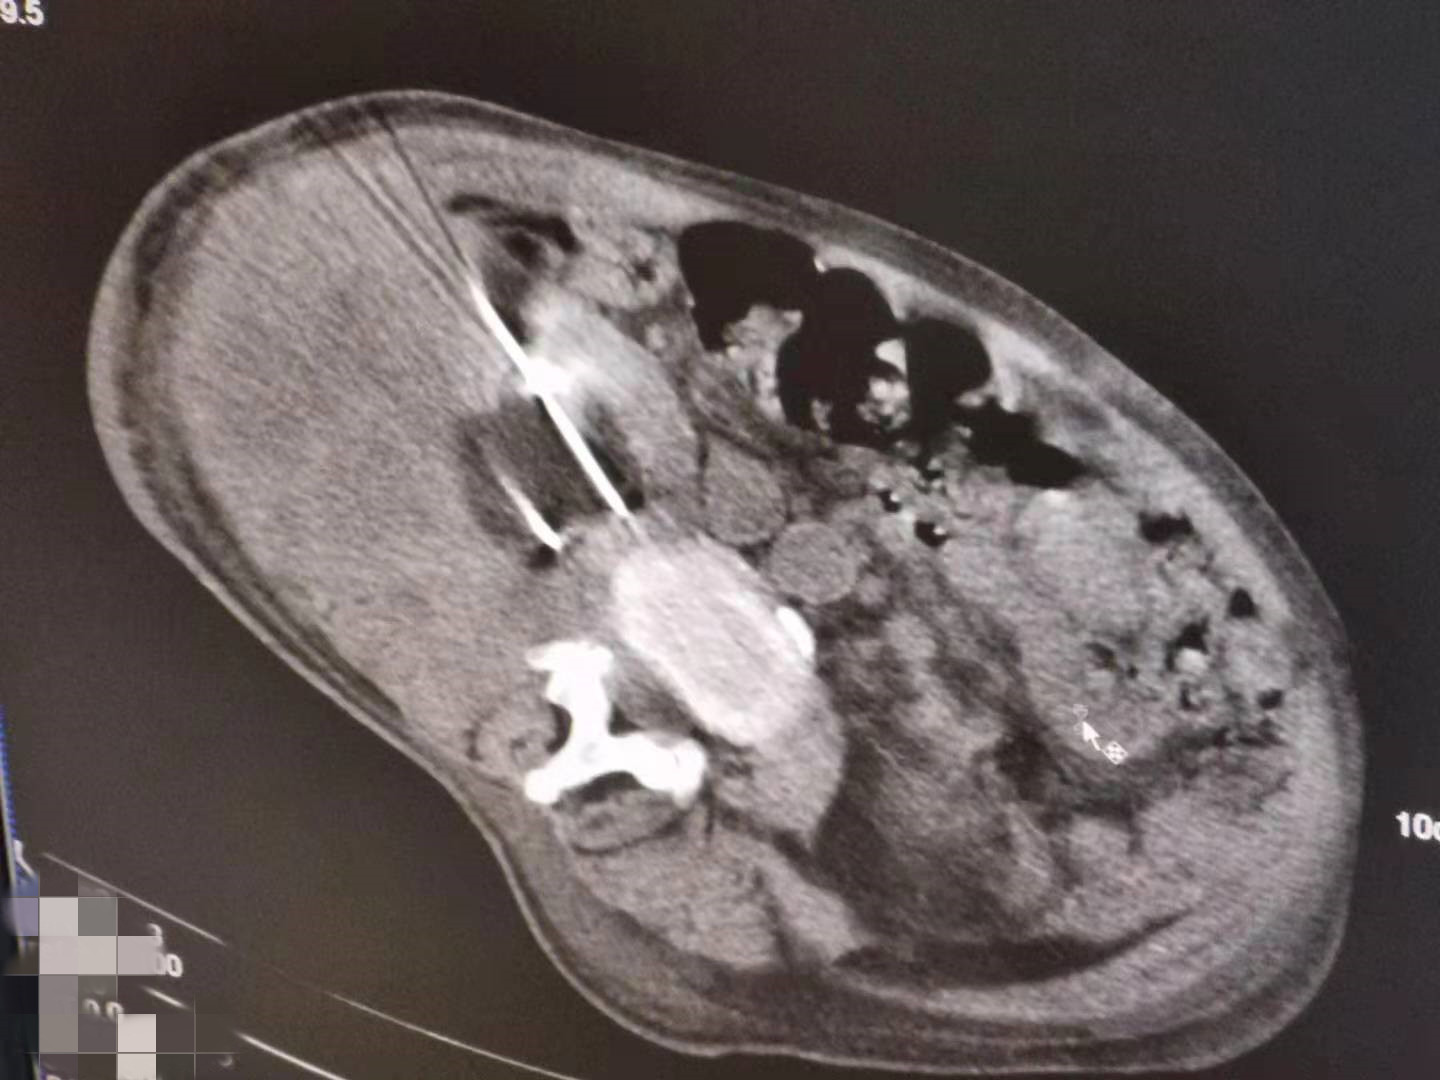

2021年5月份肾部氩氦刀手术